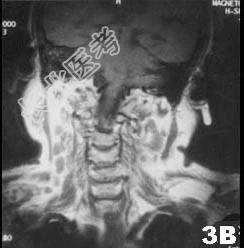

单项选择题肺结核患者发现双侧腮腺区肿块3个月,缓慢增大, 无明显症状。查体腮腺区可触及局限性肿块,边界清, 质软,可活动, 轻压痛。CT 检查结果图示。首先考虑的诊断为 ( )

A、腮腺囊肿

B、腮腺多形性腺瘤

C、腮腺结核

D、慢性腮腺炎

E、腮腺腺样囊性癌